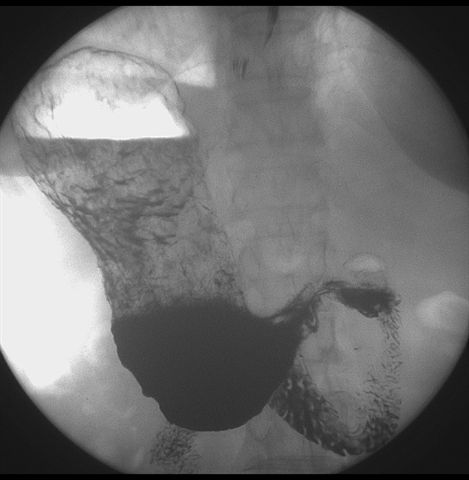

标题: X6872:F,69y,胃部不适。

胃窦至幽门段胃壁僵硬,扩张受限,局部纠集粘破坏,呈杵状。提示溃疡癌变可能性大。

胃窦癌可能性大,建议胃镜活检。钡剂太稀,吃的有点多。

支持考虑胃窦癌可能,胃内滞留液太多,胃窦部僵硬。

胃窦部见钡池影,局部粘膜紊乱,纠集呈杵状改变,胃壁扩张受限,胃窦癌可能性大,建议胃镜检查.

胃窦部管腔扩张度较差,形态略有改变,胃窦粘膜显示欠佳,胃窦部占位可能性大,结合胃镜活检。

北京肿瘤医院胃镜诊断皮革胃。